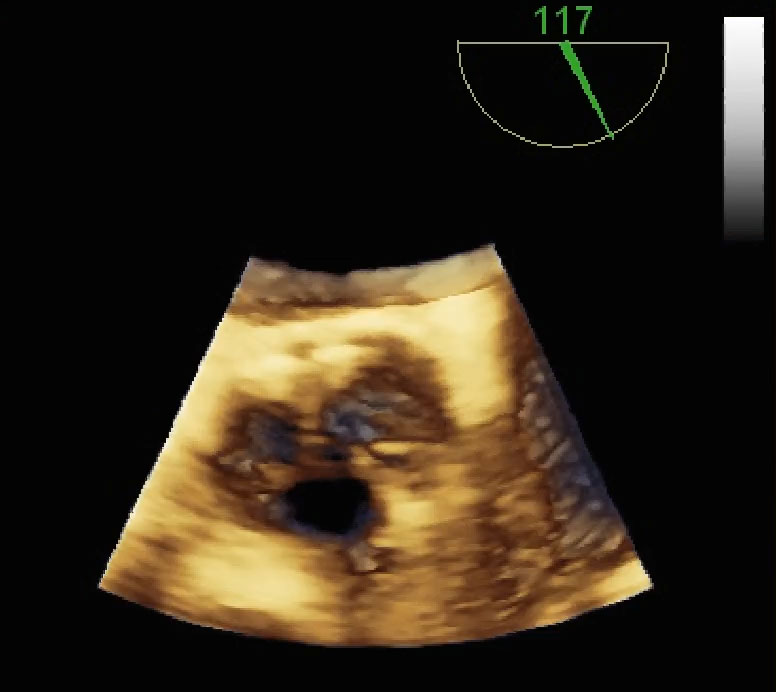

Chiusura percutanea di paraleak (protesi valvolare mitralica biologica)